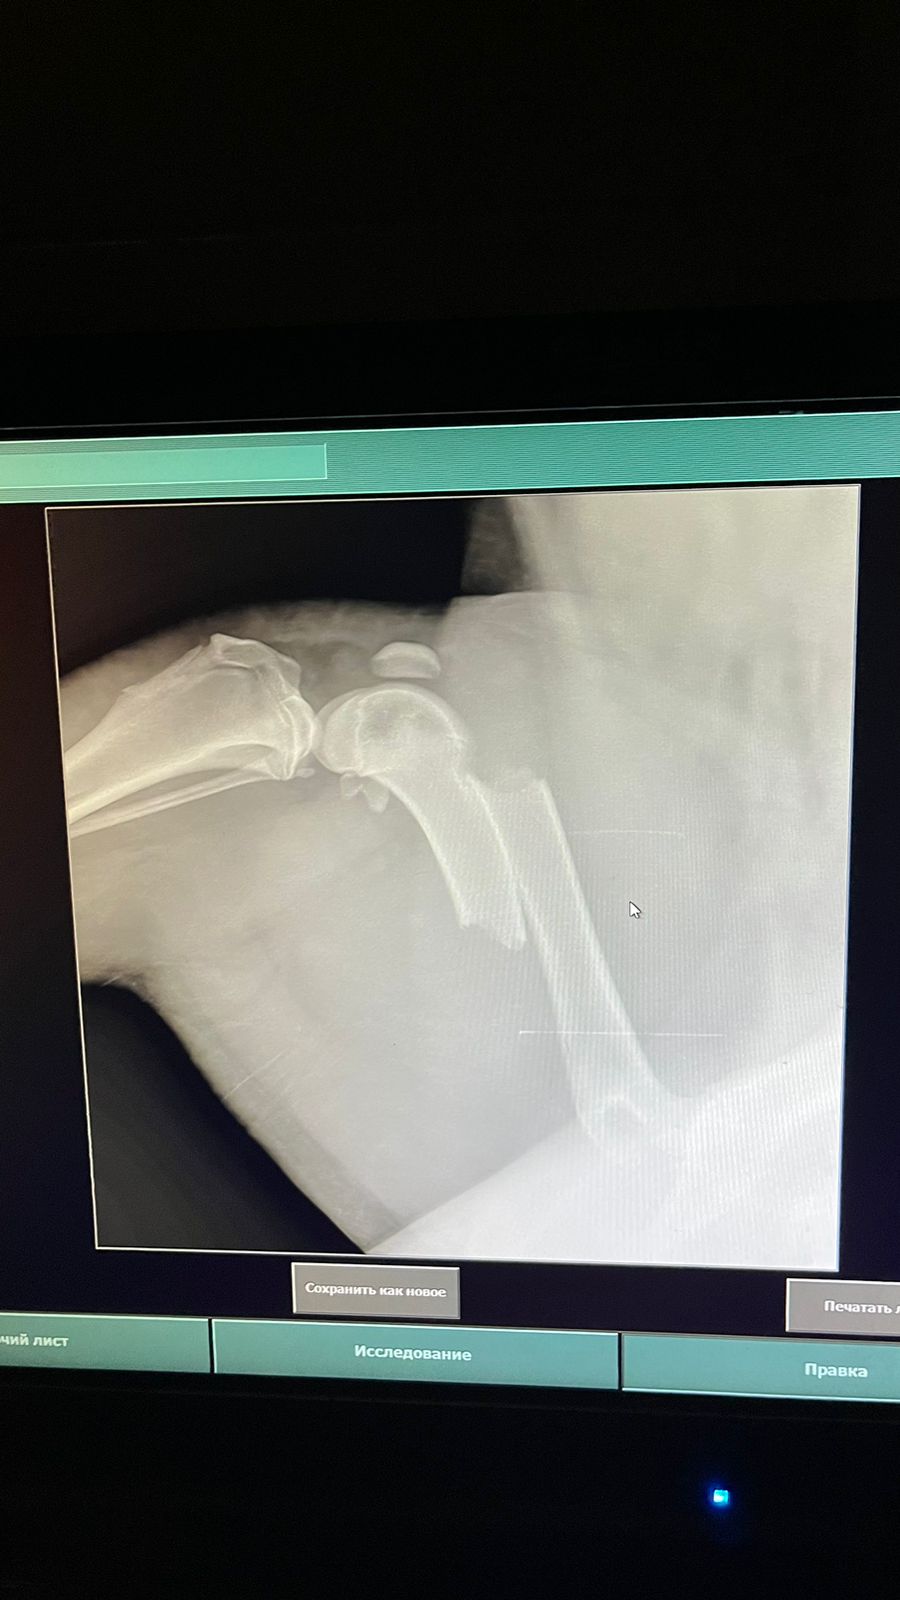

Волонтёр привела молодую суку ризена со сломанной лапой в клинику к Насте pani Stasi. Вроде перелом не сильно свежий.

Ногу будет хирург смотреть и может в ближайшее время прооперируют.

Если не дать образоваться мозоли, то все должно встать на место и будет хорошо.

Но чем больше тянуть, тем тяжелее совмещать кость....

Поэтому, чем быстрее, тем лучше. Если никаких других подводных камней нет.

Её забрала заводчица. И что-то там у них случилось, то ли лошадь понесла, то ли что, в общем, собака перепрыгивала через телегу и сломала лапу. У заводчицы тоже ключица сломана, может ещё что-то.

Операцию сделали, собрали лапу на две пластины. Выписка попозже будет.

Да, задняя правая сломана.